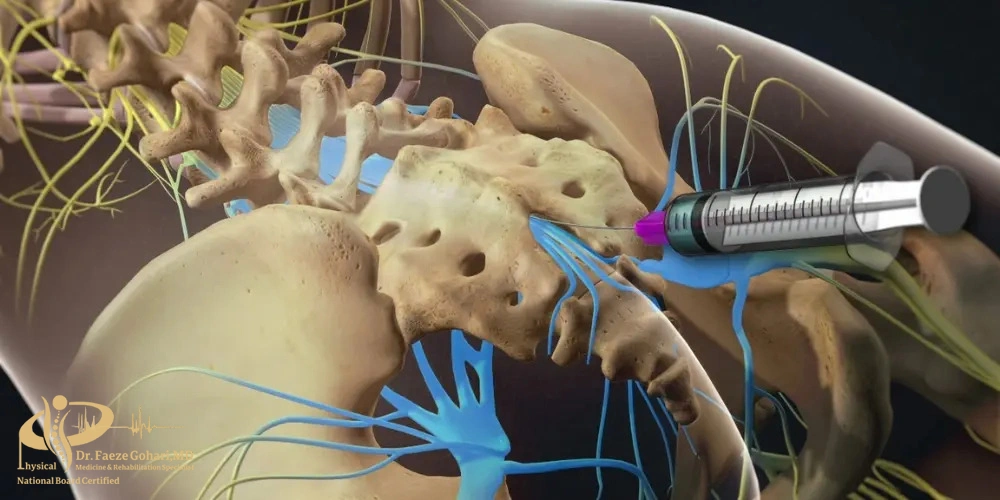

تزریق به محل عصب برای بلاک کردن مسیر انتقال پیامهای درد و علائم عصبی

عصب رشتهای از فیبرهای عصبی است که پیامهای حسی، از جمله درد، را از اندامها به نخاع و سپس مغز منتقل میکند و در واقع مسیر اصلی انتقال احساس درد به شمار میرود. در بلوک عصبی، پزشک با استفاده از یک سوزن باریک و تحت هدایت تصویربرداری دقیق، داروهایی مانند بیحسی، ضدالتهابی یا ترکیبی از هر دو را در اطراف عصب تزریق میکند. این داروها انتقال پیام عصبی را به طور موقت مختل میکنند و در نتیجه سیگنال درد به مغز نمیرسد.

در این روش، پزشک با کمک تصویربرداری (فلوروسکوپی) سوزن ظریف را در کنار عصب یا مفصل موردنظر قرار میدهد و داروهایی مانند بیحسی موضعی یا کورتون تزریق میکند. این داروها التهاب را کاهش میدهند و انتقال پیامهای درد را بهطور موقت متوقف میسازند. این روش معمولاً با بیحسی موضعی انجام میشود و بهجز سوزش مختصر یا فشار خفیف هنگام ورود سوزن و تزریق دارو، درد قابل توجهی ندارد. خود تزریق معمولاً ۱۵ تا ۳۰ دقیقه طول میکشد و اثر آن از چند روز تا چند ماه باقی میماند.